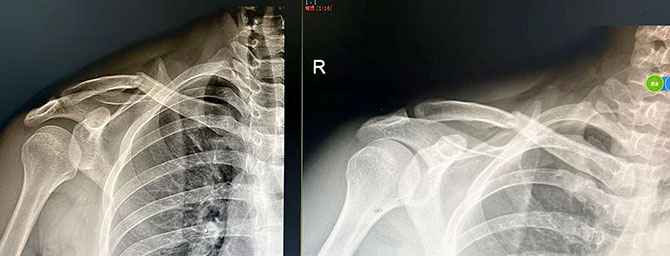

患者2:男,42岁,右侧锁骨骨折,复位前后对比

复位前 复位后